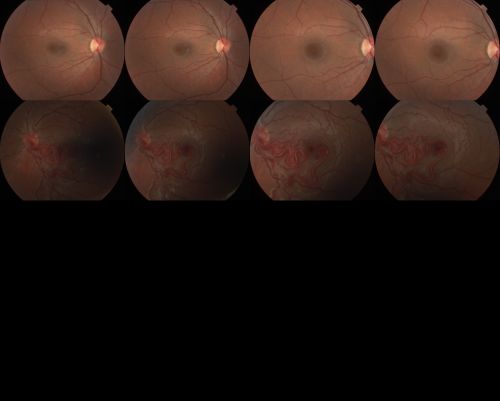

wyburn-mason syndrome fundus photos

28 year old female, visual acuity 20/200